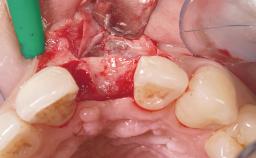

Immediate Placement of an Implant in a Maxillary Left Central Incisor Site

A 33-year-old female patient presented with an upper left central incisor that required extraction after a failed endodontic therapy. The tooth had been traumatized when the patient was a teenager and had undergone several endodontic treatments, including two apicectomy procedures. The patient was in good health and did not smoke. Clinical examination showed that the patient had a high lip line. In full smile, the gingival margins of the upper teeth were visible to the first molars. The gingival margins of central incisors 11 and 21 were only just showing. Examination of tooth 21 confirmed that the tooth was mobile and had hypererupted by 1 mm.

Bone Augmentation Horizontal|Simultaneous

Augmentation Materials Xenogenous|Membrane

Socket Integrity Damage to one or more bone walls

Bone Volume Damage to one or more socket walls